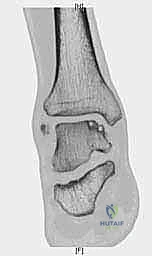

- التصوير بالرنين المغناطيسي (MRI): هو "المعيار الذهبي" لتشخيص آفات الكاحل. يوضح الرنين المغناطيسي بدقة متناهية حالة الغضروف، حجم التكيسات العظمية، ومقدار التورم داخل العظم (Bone marrow edema). من خلال صور الرنين، يحدد الدكتور هطيف أبعاد الآفة (الطول، العرض، العمق) بدقة المليمتر.

- التصوير المقطعي المحوسب (CT Scan): ضروري جداً للآفات الكبيرة. يوفر الـ CT صورة ثلاثية الأبعاد للعظم، مما يساعد الجراح في التخطيط الدقيق لعملية قطع العظم وحجم الطعم المطلوب زراعته.